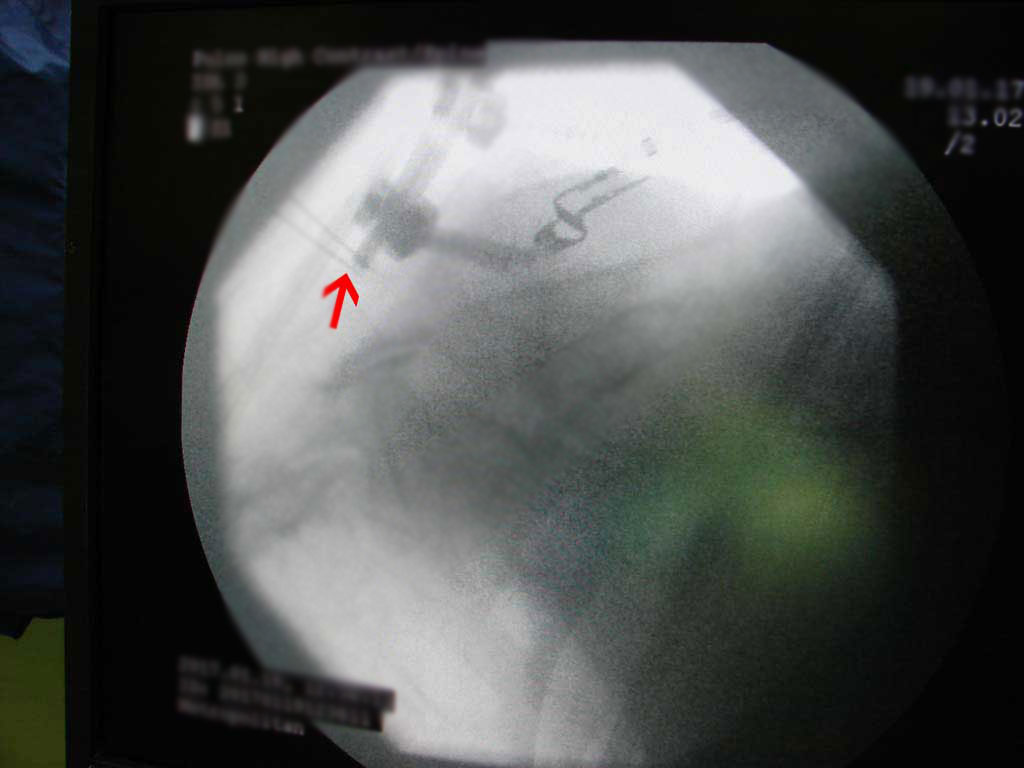

- Επίπεδα A6-A7 και Α7-Θ1